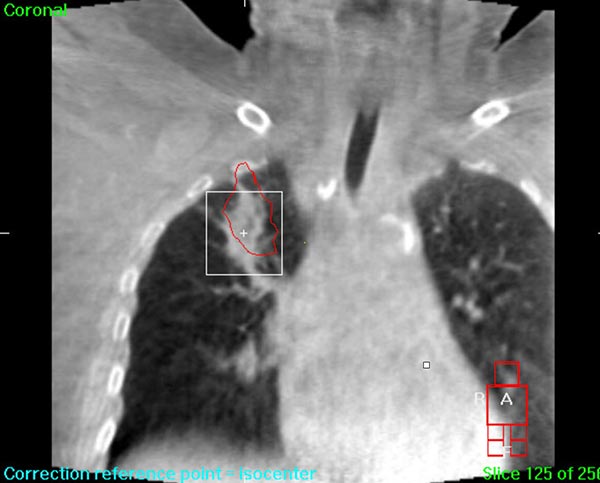

We understand that a cancer diagnosis can be scary, which is why Florida Center for Breast Conservation is dedicated to compassionate care and state-of-the-art technology. Florida Center for Breast Conservation uses the Elekta Synergy® machine, a digital accelerator for advanced image-guided radiation therapy (IGRT). It is the only all-digital treatment device in the world. This allows your doctor to view your tumor in real-time at the time of your treatment.

The 3-D high-quality images taken at the time of your treatment can be studied against your previous CT scans precisely and promptly to ensure that the doctors are treating your tumor as accurately as possible while greatly limiting any exposure to healthy tissue in the area.

Elekta Synergy® provides unparalleled clinical assurance to more aggressively treat tumors while keeping damage to surrounding healthy tissues to a minimum. Elekta Synergy®‘s precision accuracy reduces or eliminates the use of markers because clinicians can view soft tissue using Elekta Synergy®‘s VolumeViewTM. The low-dose imaging proficiency helps minimize the side effects of radiation therapy by decreasing the margins previously set to account for the unpredictability of target location, movement, and dimensions.